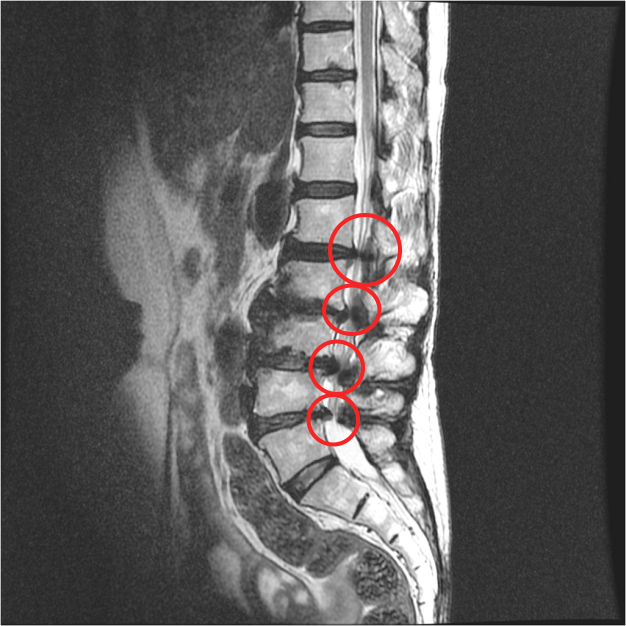

그런데, 보시면 협착증은 이 부분만이 아니라 주변 부분도 다 퇴행되어 있습니다. 그래서 고정술을 한 이후에 이 부분이 구부리지도 펴지도 못하게 되기 때문에 이미 퇴행된 주변 마디에 부담을 주게 됩니다. 주변 마디가 더 많이 구부렸다 폈다가 해줘야 하는 것이죠. 그런데 앞서 말했듯이 협착증 환자는 이미 주변 위아래 마디도 퇴행되어 약해진 상태인데, 추가적으로 부담을 주니까 시간이 흐르면 주변 부위도 문제가 생기게 되는데요. 이것을 인접분절질환이라고 합니다. 일반적으로 척추유합술 후 이러한 문제가 많이 발생하기 때문에 인접분절질환이라는 이름까지 만들어져 있습니다. 이러한 인접분절질환은 특히 수술 후 관리를 잘 못하면 당연히 더 잘 생기기 때문에 유합술을 했다면, 이 인접분절질환이 생기지 않도록 관리를 세심하게 잘 해줘야 합니다.

척추협착증 수술에 많이 하는 척추유합술, 유합술 후 발생하는 인접분절질환에 대해 꼭 알아야 합니다